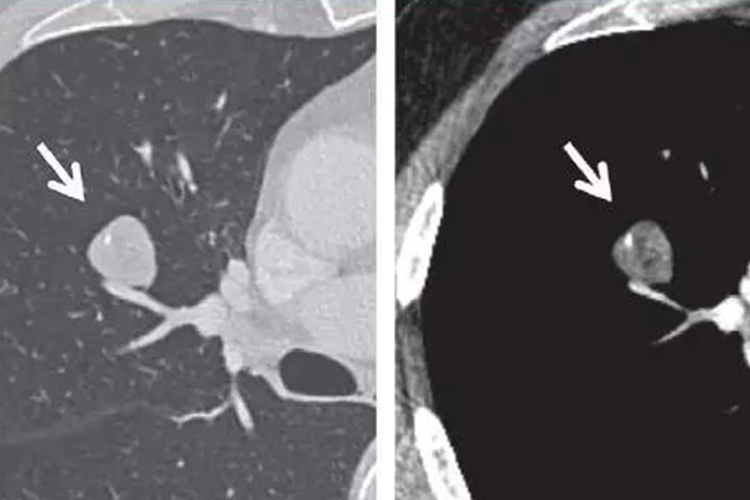

肺部错构瘤CT表现为病灶边缘光滑,多呈圆形或类圆形,无毛刺征,可有轻度分叶,病灶多小于5cm,肿块多为软组织密度,其内可见脂肪密度区。肿块多位于肺内,可靠近肺门,亦可位于气管腔内,肺门及纵隔内无肿大淋巴结。